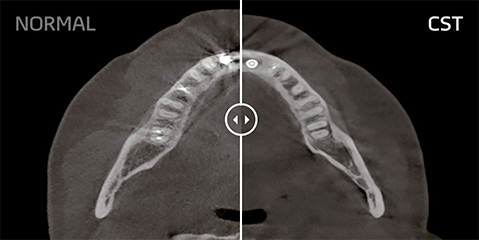

Compressed Sensing Technology

Vatech migliora in modo significativo la qualità dell’immagine, riducendo drasticamente artefatti e rumore grazie alla Compressed Sensing Technology (CST). Attraverso un processo di ricostruzione iterativa eseguito fino a 10 volte in più rispetto agli standard tradizionali, il sistema riesce a rappresentare l’oggetto in modo più fedele e accurato. La modalità di scansione cefalometrica offre due formati di immagine, LAT e FULL LAT, selezionabili in base alle specifiche esigenze diagnostiche.